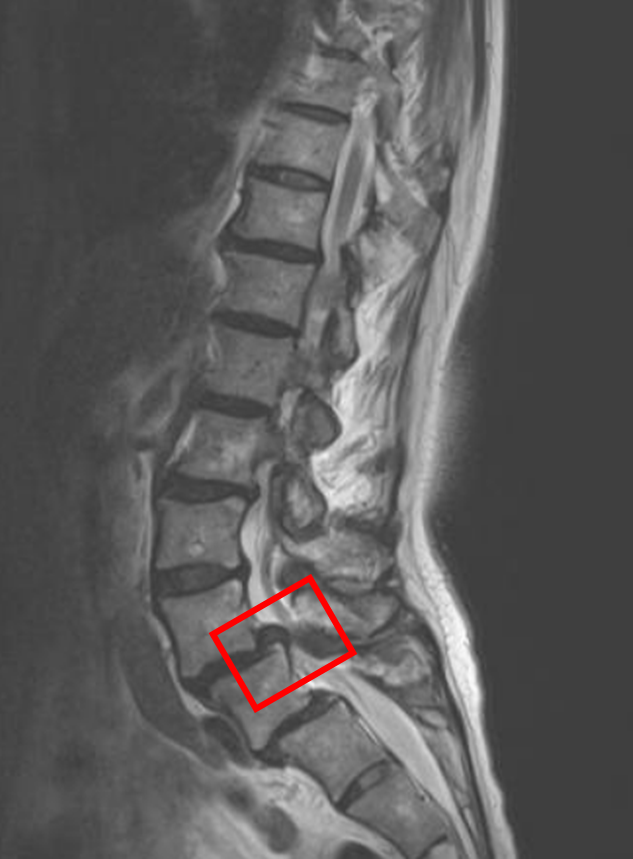

この患者様は赤い枠で示されている箇所(L4/5)に脊柱管狭窄症を認めます。

L4・L5共にすべり症を認めます。